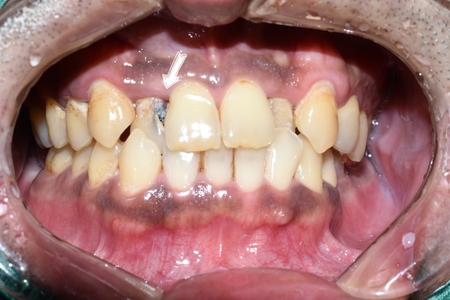

앞니가 많이 썩은 환자분으로,

보이는 앞니의 충치 뿐만 아니라 보이지 않는 입천장 쪽의 충치, 치아 사이 속의 충치도 있었습니다.

앞니 충치 치료전

앞니 4개 모두 충치치료가 필요한 상태입니다.

매우 심한 충치는 충치 부위가 신경부위까지 닿아있어 신경치료도 시행하였으며

그 외 치아는 레진 치료 시행하였습니다.